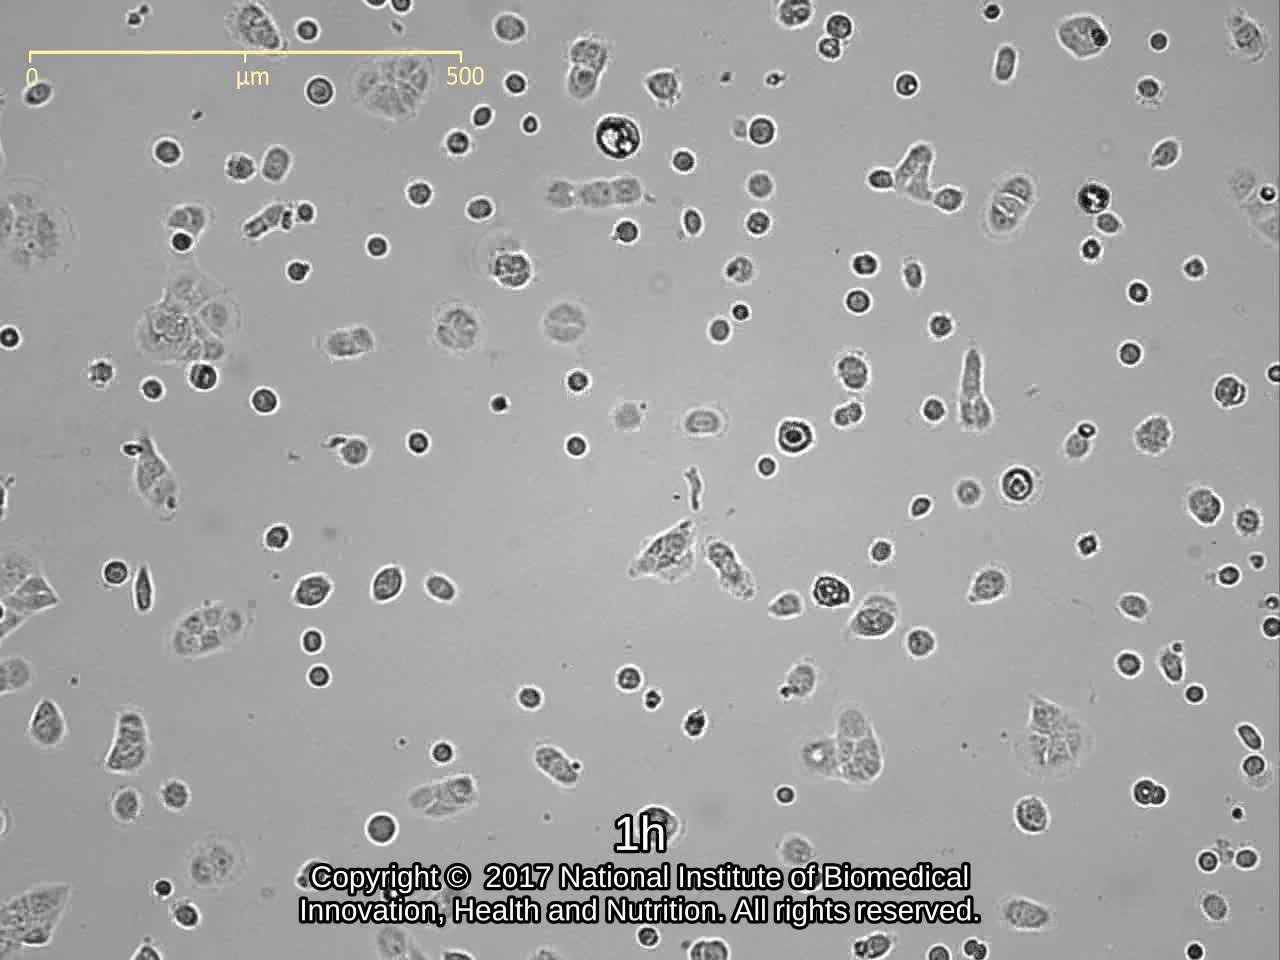

| Images |

![]() ![]() ![]() ![]() ![]() ![]() ![]() ![]() ![]() ![]() ![]() ![]() ![]() ![]() ![]() ![]() ![]() ![]() ![]() ![]() ![]() |